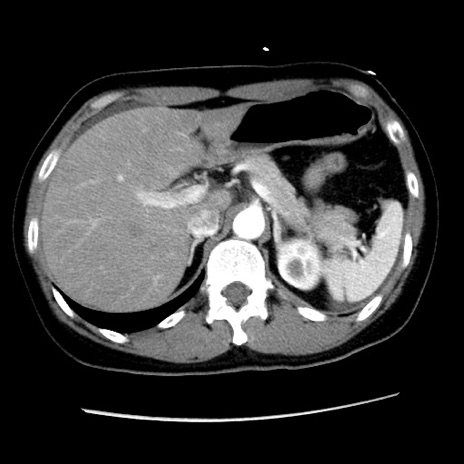

矢状断像

【症例】 50歳代女性

【主訴】 腹痛

【現病歴】前日生レバーを食べた。今朝に排便あり。 昼前に突然発症の腹痛を生じ、当院救急外来を受診した。

【身体所見】 意識清明、腹部:平坦、軟、下腹部やや左を中心に圧痛・反跳痛あり、筋性防御あり